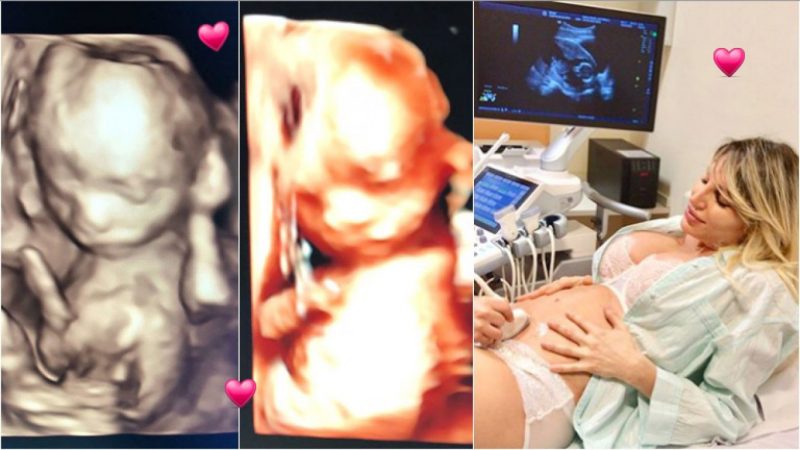

Feliz de vivir cada nueva sensación de llevar en su vientre a su primer hijo, Vicky compartió con sus seguidores varias postales de la ecografía 4D con la carita de Salvador Uriel, su bebé en camino: “Y con ustedes, les presento al milagro de cuatro meses @salvadorurielok”, escribió en Instagram.

“¡¡¡Hoy cumple 18 semanas, ya mide como un pimiento y me regalo estas imágenes. Es la primera vez que le conozco la carita y no quería dejar de compartirlo con ustedes!!!! #SeMeExplotaElCorazónDeFelicidad. ¿¿Lo ven parecido a mí???? #HijoTeAmo #SalvadorUriel”, cerró, emocionada por esta hermosa etapa de su vida.

¡Conocé la carita de Salvador Uriel, el bebé en camino de Vicky Xipolitakis y Javier Naselli!